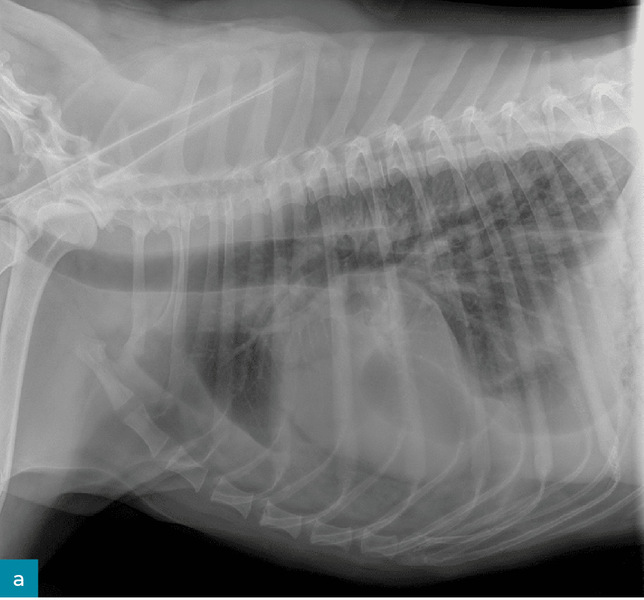

Lekarz weterynarii podstawowej opieki zdrowotnej poinformował, że badanie kliniczne pacjenta było w normie: temperatura wynosiła 38,2°C, częstość pracy serca 90 uderzeń/min, a częstość oddechów 35/min przy normalnym wysiłku. Odnotowano utratę masy ciała o 2 kg – podczas corocznego badania sześć miesięcy wcześniej wynosiła ona 33 kg. Wykonano przesiewowe badanie rentgenowskie jamy brzusznej oraz klatki piersiowej i zidentyfikowano płyn w przestrzeni opłucnowej (ryc. 2). Pacjent został skierowany do placówki specjalistycznej/ratunkowej w celu przeprowadzenia dodatkowej diagnostyki.

• Medium 1268

• Medium 1306

Ryc. 2. Prawe profilowe (a) i brzuszno-grzbietowe (b) zdjęcie klatki piersiowej pacjenta z chłonkopiersiem, pokazujące płyn w przestrzeni opłucnowej.

W ośrodku ratunkowym pacjent był ożywiony, czujny i reagował na bodźce. Stwierdzono szmer skurczowy serca stopnia 2/6. Radiogramy klatki piersiowej potwierdziły płyn w jamie opłucnej i wykazały łagodną niedodmę doogonowych pól płucnych. Podczas nakłucia klatki piersiowej usunięto około 3 ml białego, mlecznego płynu z lewej doczaszkowej części klatki piersiowej i około 20 ml z prawej części klatki piersiowej. Rodzaje płynu gromadzącego się w przestrzeni opłucnej obejmują przesięk, zmodyfikowany przesięk, wysięk oraz wysięk limfatyczny. Biorąc pod uwagę wygląd płynu, podejrzewano wysięk limfatyczny. Ostateczne rozpoznanie chłonkopiersia opiera się na wykryciu w płynie stężenia triglicerydów wyższego niż w surowicy. Płyn został przesłany wraz z krwią i moczem do badań diagnostycznych.